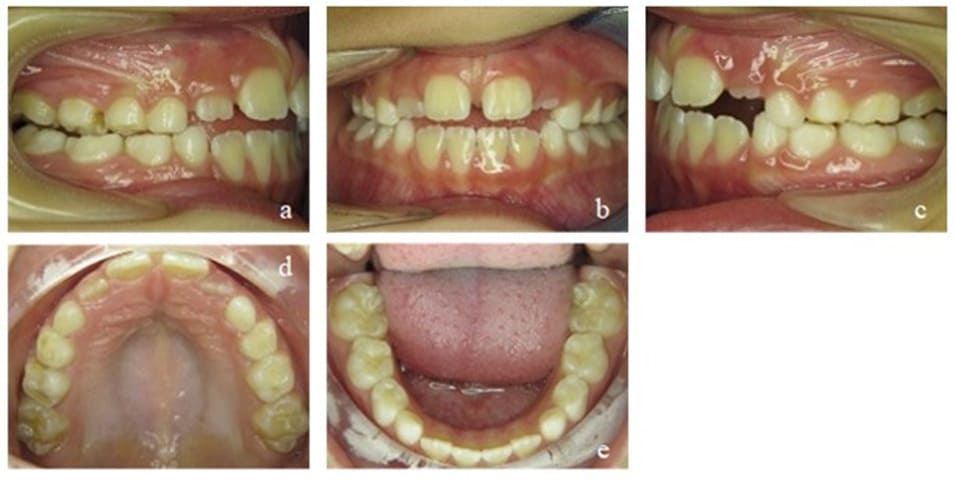

In the last active treatment phase as well as sustainable phase, the patient continued wearing an EGA. For the first time, we achieved a positive overbite, and the patient could fully establish a closed lip posture with nasal breathing. The tongue could be strengthened, and the resting position was stable in its physiological state. However, for a long time, there was still no contact of the upper and lower front teeth. This could be fully achieved 2 years later and stayed stable in the long term (Figure 13).

Figure 12: Case 2. Second Interims findings after 12 months of treatment. Frontal view of the occlusion (b), occlusion right (a) and left (c). Upper (d) and lower arch (e).

Figure 13: Case 2. Third interims findings after 18 months of treatment. Overjet and overbite (b), occlusion right (a) and left (c). Upper (d) and lower arch (e).